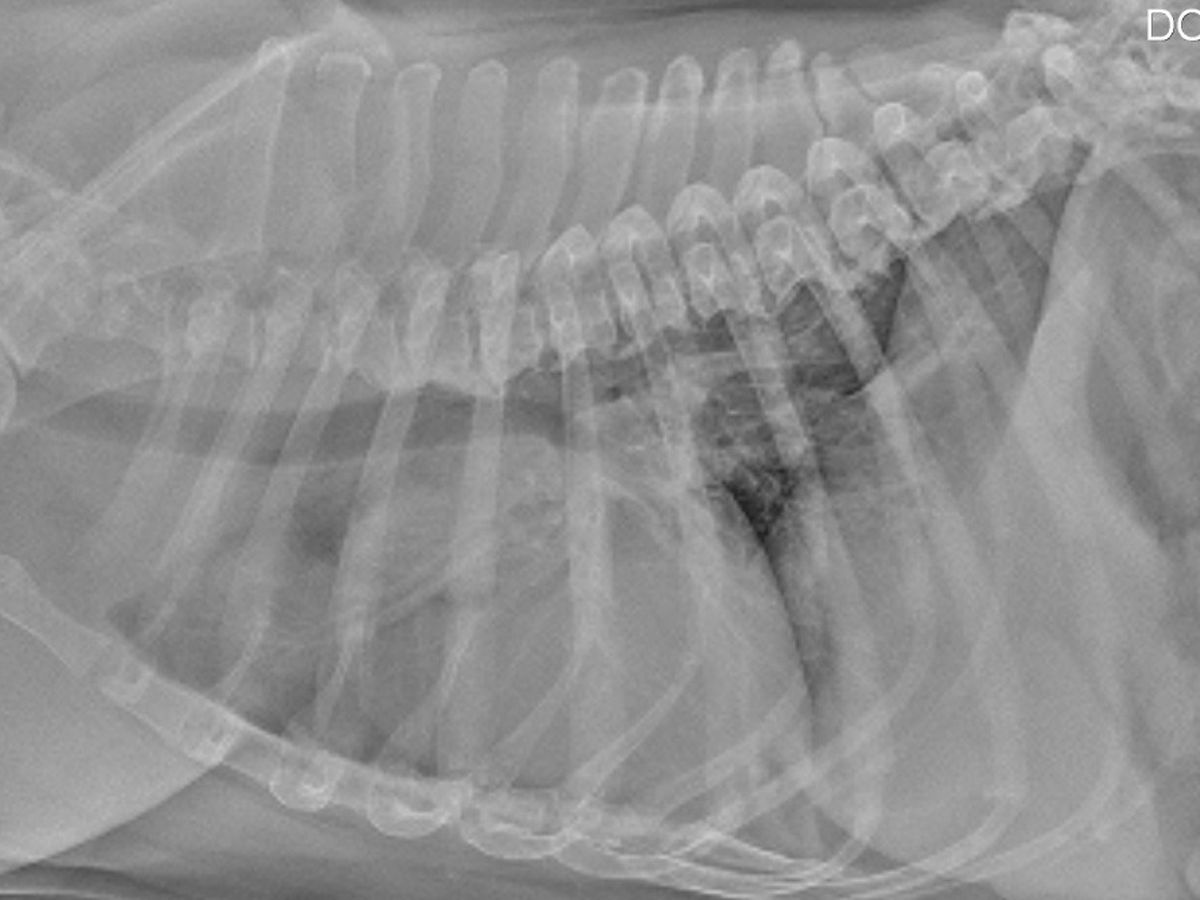

I know one day I will have to accept I have to say goodbye to Czr but I am just not ready to accept that time is now. We've been hit with a series of events & I just can't keep up with the costs. It started on about August 5th when Czr had started getting diarrhea. He's a super sensitive pup, so it's not uncommon for him to get the runs for a couple days, so I fasted him to see if it was something that would clear up on its own, or if there was the possibility of him catching giardia again (he gets it 1-3x a year since he's susceptible after catching it as a puppy & there's a river nearby & too many people that don't clean up after their pets downtown). By that Friday he was refusing to even drink water anymore so I rushed him into an emergency clinic. There he was given metronidazole to treat giardia and Cerenia to calm his tummy. Within 10 hours & lasting around another 10, Czr experienced quite extreme grand mal seizures. His stomach was already much better from treating the giardia) but I still followed up with a blood and urine test with his regular vet on the Monday. At that point, his creatinine levels were elevated to 224 & I was advised to rush him into emergency as he was basically toxic. We spent 6 days in emergency, keeping him on fluids & antibiotics but by the end I had spent thousands & his CREA level was now up to 315. I was watching him deteriorate in front of my eyes & no one really understood why. To have his creatinine levels that high is indicative of the loss of more than 75% of his kidney function. All they can say is that he suffered some sort of a toxic insult to his kidney which was causing acute kidney failure: I am happy to report that within the last week at home I do have that level down to 211 (it needs to get under 159 - but I have faith we can do it), but he has elevated globulins which could be from a variety of issues, but my main concern is a mass we found in his chest that could indicate cancer.

Our next steps include aspirating the mass under an x-ray & further imaging to try to narrow down what it may be. We attempted a fasted ionized calcium test to check for a specific type of tumor but it was negative. I know Czr can fight this... he's shown over this past week he's not ready to go. So if you can help me at all, I will be eternally grateful.